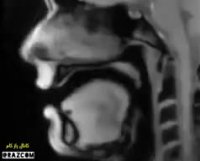

فیلم جالب MRI از صحبت کردن یک انسان - به حرکت زبان توجه کنید